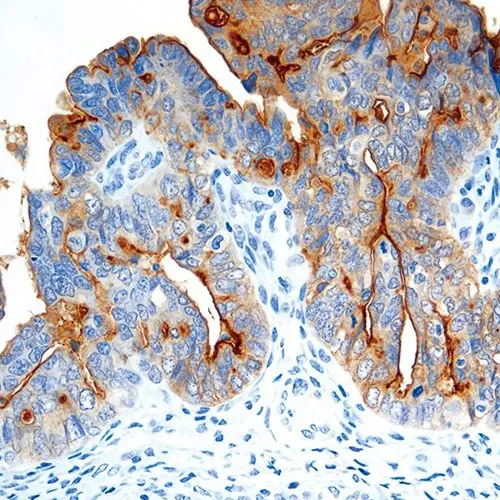

Folate is a basic component of cell metabolism and DNA synthesis and repair. It is involved in essential one-carbon transfer reactions and is a vitamin required by both normal and tumor cells. Folate entry into cells is facilitated via two different systems: the reduced folate carrier, which utilizes a bidirectional anion-exchange mechanism, and the folate receptor system. Folate Receptor Alpha is a membrane-bound member of the folate receptor family, facilitating folate transport via a mechanism termed potocytosis where the receptor is internalized and then recycled back to the cell membrane. Staining patterns are both membranous and cytoplasmic due to this mechanism. Members of the folate receptor family share highly conserved sequences in the open reading frames, but differ in amino acids in the 5' untranslated regions and as a consequence can differ in function and tissue expression. Folate receptor alpha expression is reported to be highly restricted in normal tissues and only selectively overexpressed in a limited number of epithelial malignancies.

Folate Receptor Alpha is recommended for the detection of specific antigens of interest in normal and neoplastic tissues, as an adjunct to conventional histopathology using non-immunologic histochemical stains.